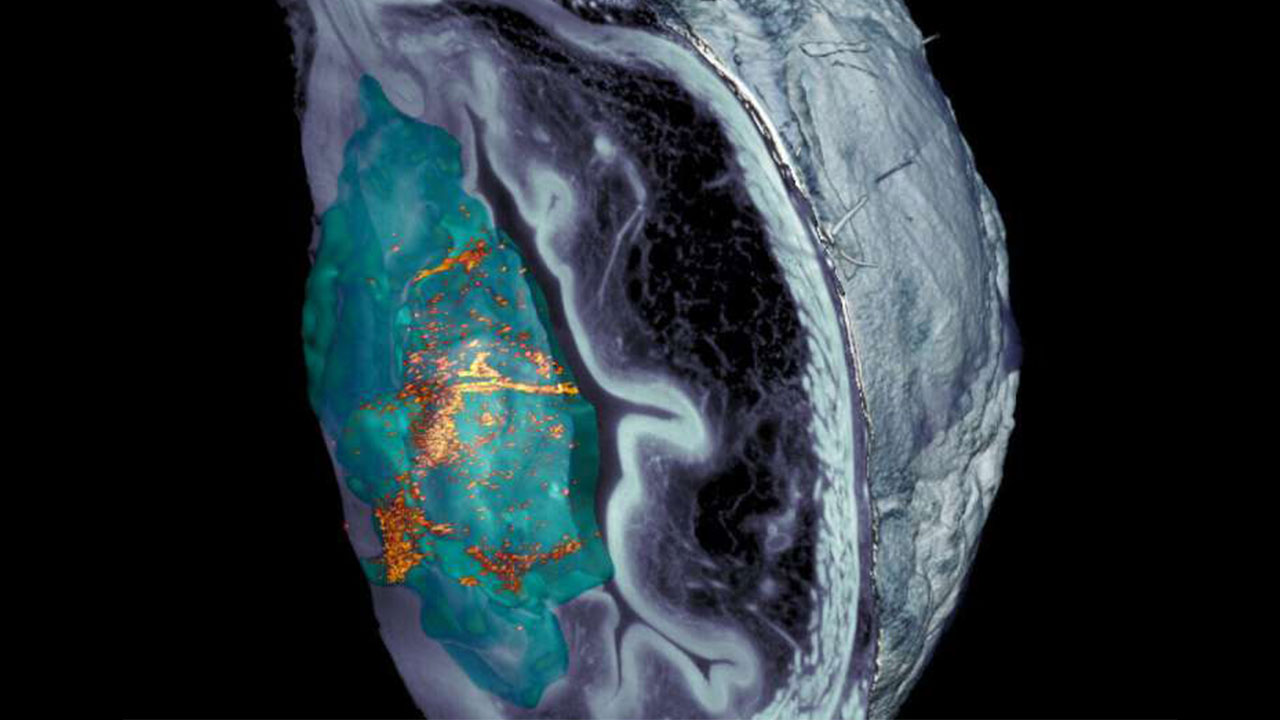

این نانوماشینهای کوچک از یک کره متخلخل ساخته شده از سیلیس تشکیل شده اند. سطوح آنها دارای اجزای مختلف با عملکردهای خاص است. یکی از این اجزا، آنزیم اورهآز است، پروتئینی است که با اوره موجود در ادرار واکنش میدهد و با این کار نانوذره را قادر میسازد خود را به حرکت درآورد.

یکی دیگر از اجزای مهم ید رادیواکتیو است، رادیوایزوتوپی که معمولا برای درمان موضعی تومورها استفاده میشود.